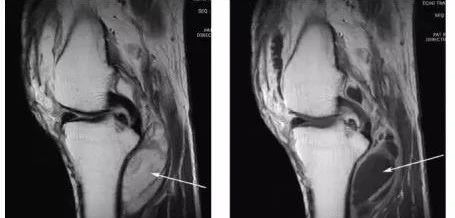

5、神经病性关节:神经病性关节病(neurogenic arthropathy,NA)又称Charcot关节,是由关节本体感觉、痛觉障碍,失去保护性反应,反复遭到损伤而引起的继发性关节病。早期关节红肿、发热,多无疼痛,少数可有持续性疼痛,关节活动时疼痛加剧。晚期由于关节囊和韧带松弛,发生关节半脱位或完全脱位。